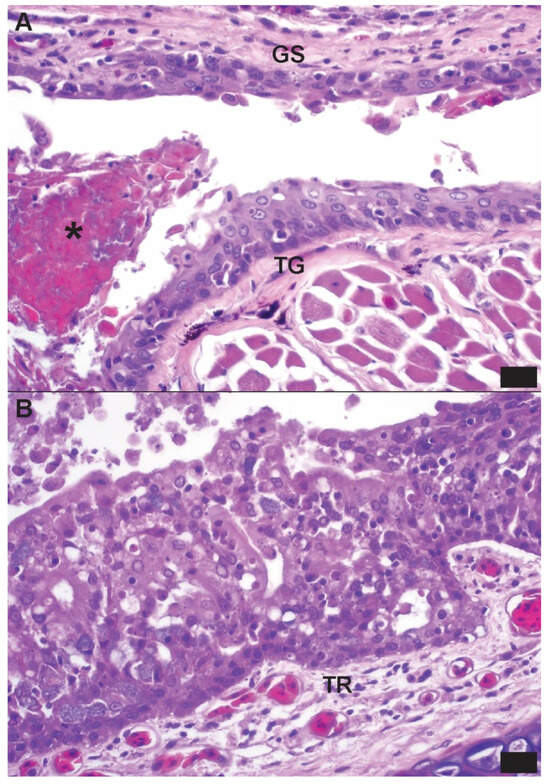

Lesions were most consistently noted in the lung, nasal cavity, oral cavity, and esophagus. Gross pulmonary lesions included wet (edematous) parenchyma and thickened faveolar septa. Microscopic lesions included mixed mononuclear and granulocytic inflammation and mucosal/epithelial changes (necrosis, hyperplasia, and erosion) in the nasal cavity, trachea, oral cavity, and lung (Figure 1).

Figure 1. Photomicrographs from a Wagler’s pit viper (Trimeresurus wagleri), the index case of a group of confiscated viperid and elapid snakes that were rtPCR-positive for novel serpentoviruses (Clade C in this snake). Hematoxylin and eosin; bar = 10 µm. (A) The mucosa of the tongue (TG) and glossal sheath (GS) exhibit characteristic epithelial proliferation and necrosis observed in ophidian serpentovirus infections in other snakes. There is also mild mixed granulocytic and lymphoplasmacytic inflammation of the mucosa and submucosa at both sites. An aggregate of necrotic cellular debris and bacteria (*) is present in the potential space of the glossal sheath, consistent with concurrent bacterial infection. (B) The tracheal mucosa exhibits diffuse and severe epithelial proliferation, loss of apical cilia, and mixed granulocytic and lymphoplasmacytic inflammation admixed with individual epithelial cell necrosis. Fewer numbers of similar mixed inflammatory cells are present in the submucosa (TR).